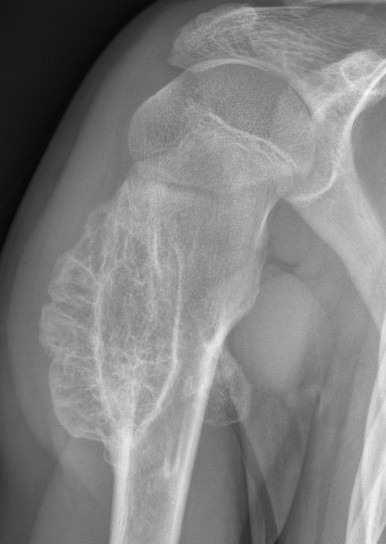

X-ray

Cortical and marrow continuity

Types

1. Pedunculated - has a stalk, points away from joint

2. Sessile - attaches to bone with a broad base

Pedunculated

Protuberant bony lesion arising adjacent to physis

- directed away from joint

- cortical bone and marrow space continuous

Sessile